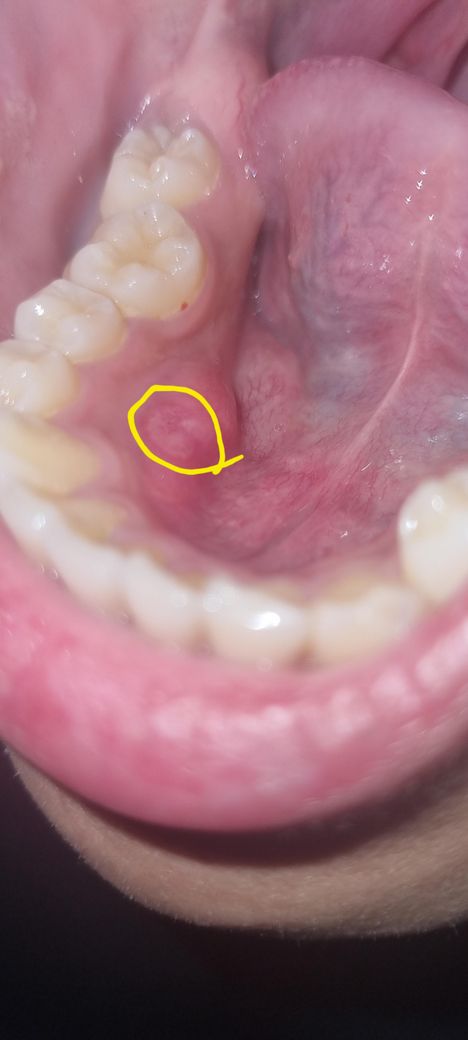

일반적인 구내염은 아닌 것 같습니다.

보다시피 퍼져있는 형태입니다

난지는 일주일 정도 됐고 혀로 누르면 아플때도 안아플때도 있습니다만 손톱으로 누르니 아프면서 살점 같은게 조금씩 떼지기도 하더라고요

나을 기미가 안 보이는것 같아서 질문을 남겨봅니다(사실 흡연으로 인해 안 낫는 것 같긴 합니다)

실제로는 사진보다는 살짝 더 하얀 색의 모양입니다